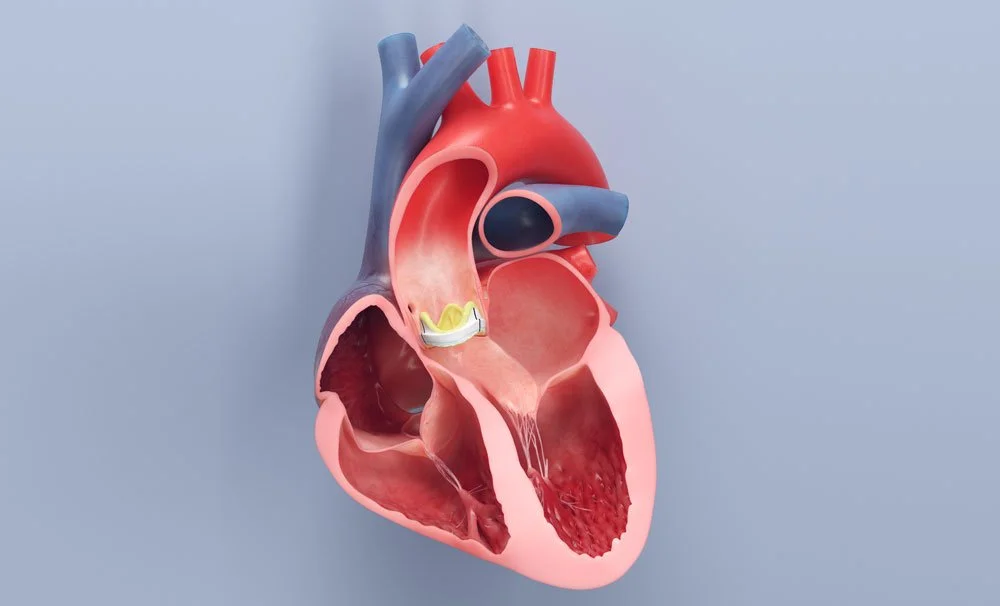

We are no strangers to the life sciences. Our medical animations animations can show how molecules interact in the body, how surgical procedures are performed, or how a new drug works at the cellular level. These visual aids help healthcare professionals, researchers, and patients understand complex medical concepts and procedures more easily.

We can help you showcase your medical device. Whether you need to present to potential investors or peers, we can create a display that will catch the attention of your audience.

We specialize in a wide variety of medical visual communications. Take a closer look:

Medical Illustration